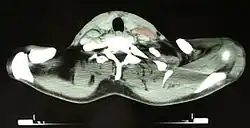

CT image of a 46-year-old person with Hodgkin lymphoma, image at neck height. On the left side of the person's neck enlarged lymph nodes are visible (marked in red).